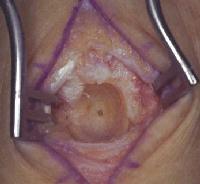

Tumor excision, burring down the dorsal capitate...